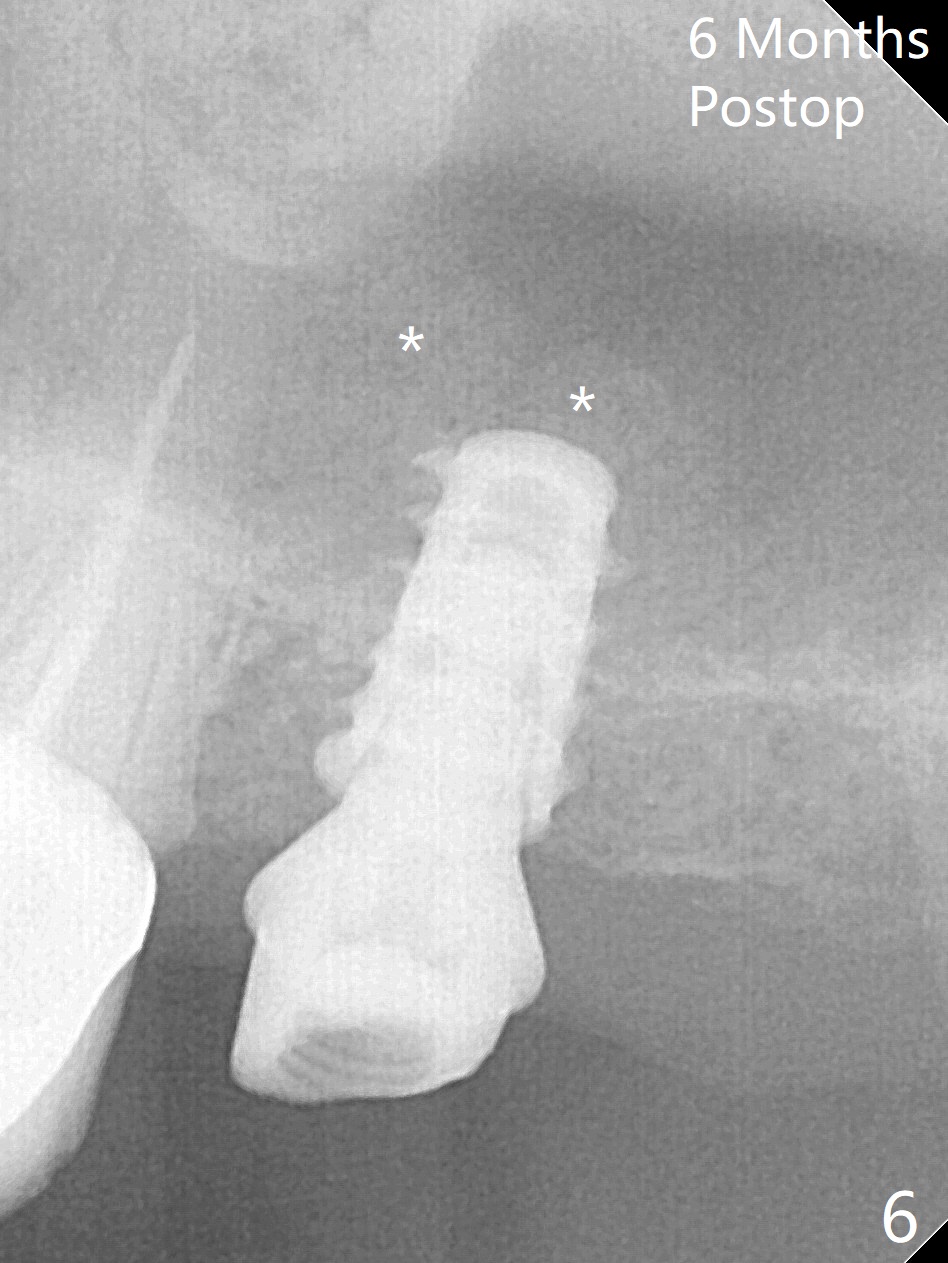

After removal of the mesial (M) and distal (D) residual roots of the tooth #15 (Fig.1,2), Magic Split is used to test bone density (high), followed by Magic Drills from Magic Sinus Lift Kit (for 4 mm) and Magic Surgical Kit (for 5 mm). It appears that the sinus floor has been perforated with the intact sinus membrane. Following minimal use of Magic Lifter, Vanilla Graft is inserted (Fig.3,4 *) and a 4x9 mm dummy implant is placed. After placement of more allograft (Fig.5 *), a 5x7 mm implant is placed with ~ 35 Ncm. With placement of a 5.5x4(2) mm abutment, an immediate provisional is fabricated to close the socket. Six months postop, the bone graft remains in the sinus around the apical end of the implant (Fig.6 *), while there seems no bone loss coronally (Fig.7). In fact there is, as shown later (Fig.8-11 < and lingual (L)). The crown is recemented 6 months post cementation (due to short abutment). The abutment seems to be incompletely seated. When the crown at #14 is reprep following #13 implant, the abutment screw is being untightened, the crown dislodges first. The abutment is confirmed short with more than enough occlusal clearance. After use of 5.5 and 6.0 mm bone profile drills, a 5x4(3) mm abutment is placed with complete seating.